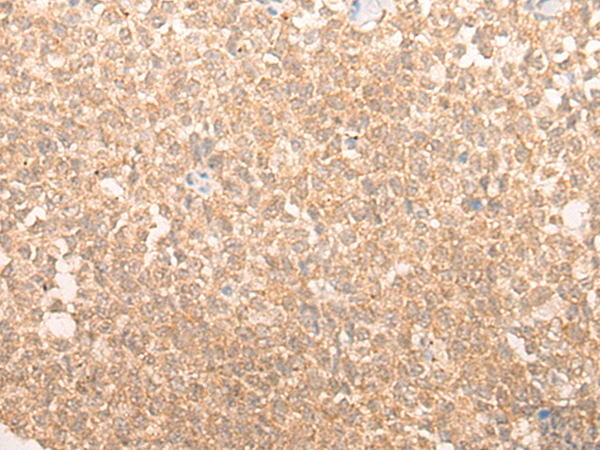

分类: 科研抗体货号: P12417别名: CGA应用: WB,IHC反应种属: Human, Mouse, Rat